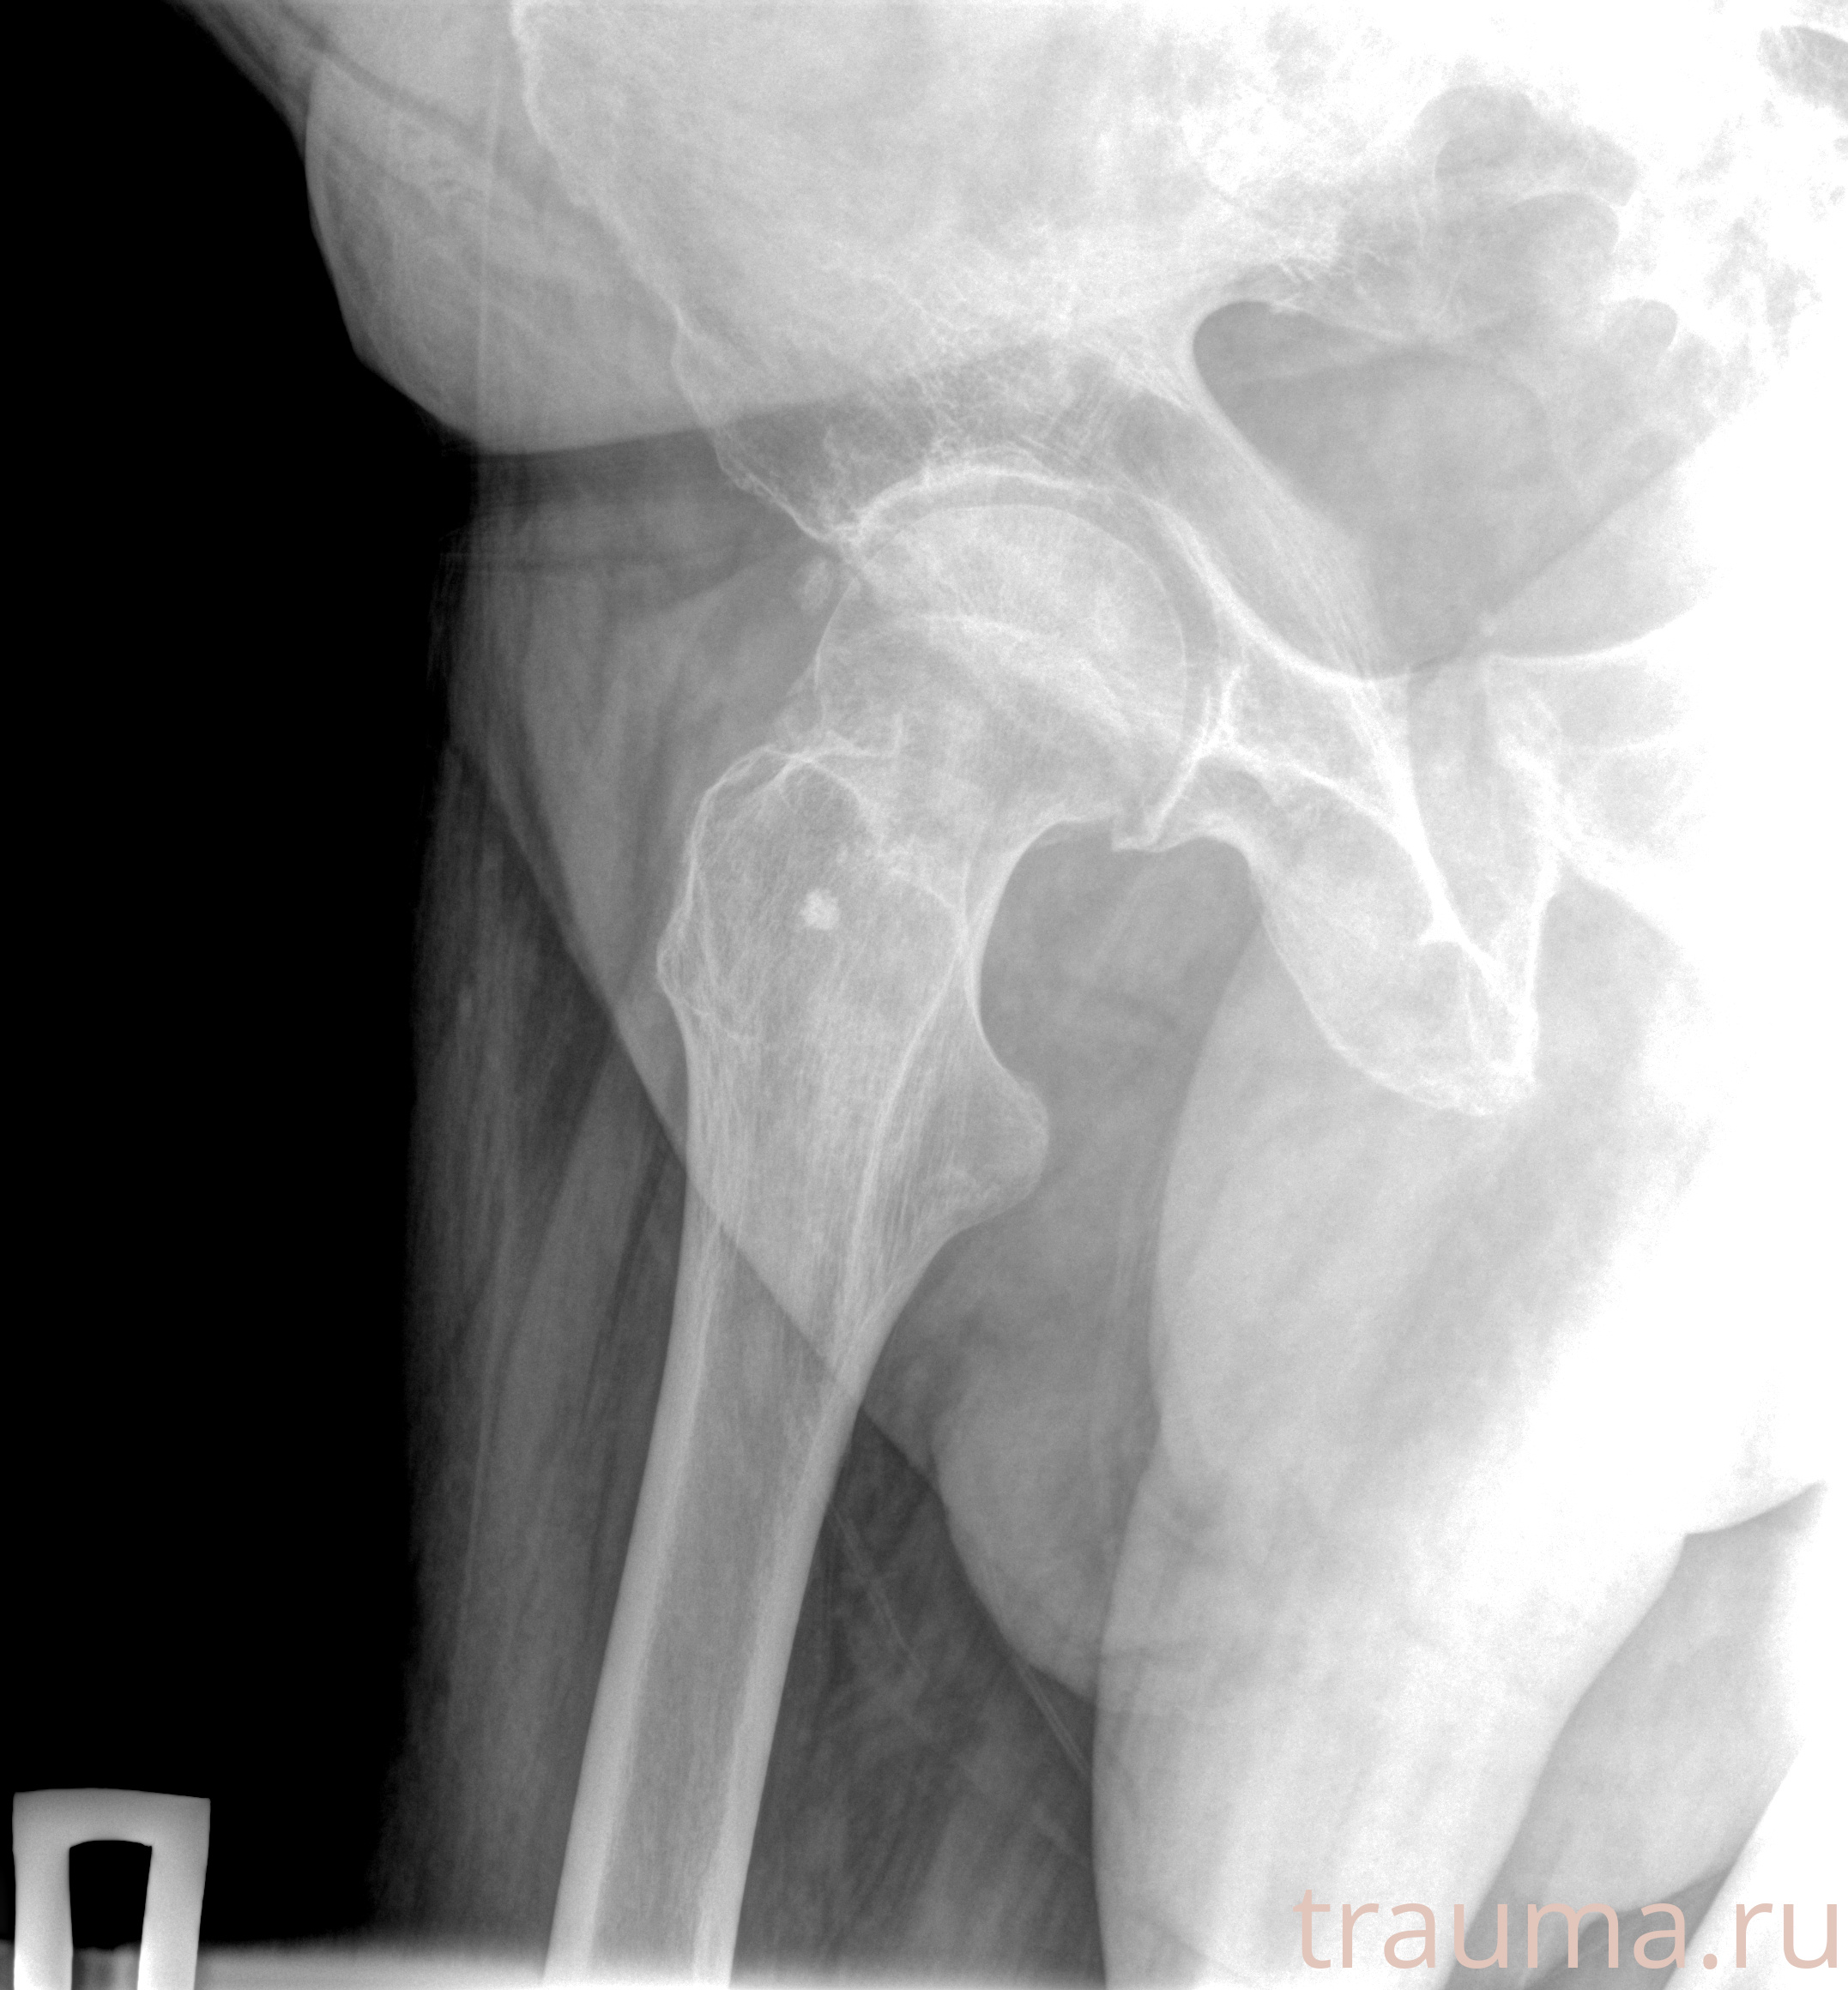

Рентгенограммы

Рентген на дому: по вашему адресу приезжает врач-рентгенолог, травматолог-ортопед с мобильным рентгеновским аппаратом, проводит диагностику травмы или заболевания, делает необходимые рентгенограммы, дает рекомендации по дальнейшему лечению. Получить качественные снимки в домашних условиях возможно благодаря уникальной методике, разработанной МосРентген Центром для института  Склифосовского